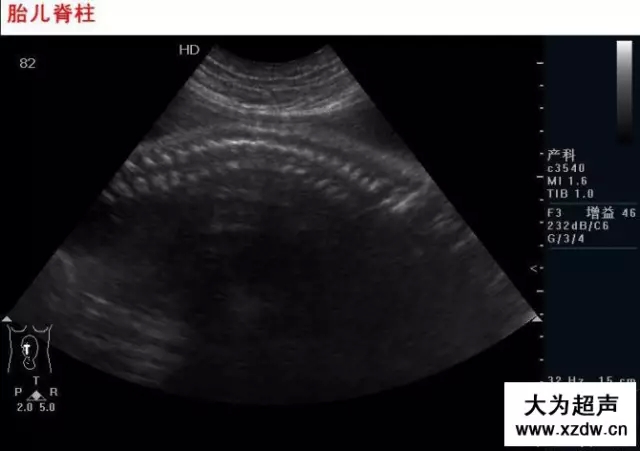

產(chǎn)科超聲正常圖片